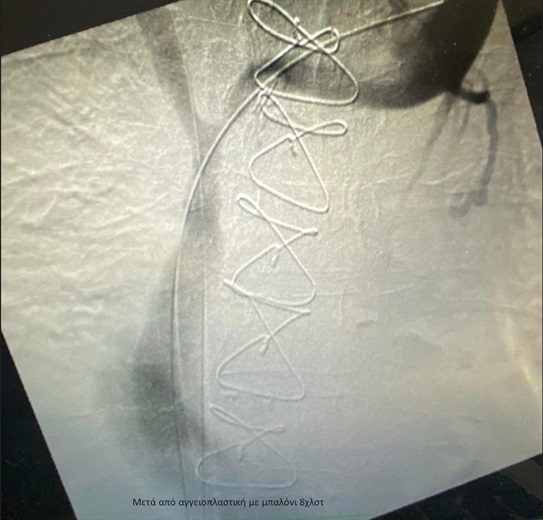

Η ομάδα της Α´ Αγγειοχειρουργικής κλινικής υπό την καθοδήγηση του Διευθυντή Αγγειοχειρουργού Νεκτάριου Γαλάνη και την πολύτιμη συνδρομή του Ακτινολόγου Βασίλειου Δημαρέλου και του Αναισθησιολόγου Δημήτριου Ζωσιμίδη, προχώρησε σε αγγειοπλαστική των πλέον στενωτικών σημείων των ανώνυμων φλεβών και της άνω κοίλης φλέβας υπό ακτινοσκοπική καθοδήγηση. Η προσπέλαση ήταν διπλή με παρακέντηση των μασχαλιαίων φλεβών αμφότερων των άνω άκρων και τοποθέτηση δίδυμων στεντ εύρους 12χλστ και μήκους 80χλστ στη δεξιά και αριστερή ανώνυμη φλέβα και την άνω κοίλη φλέβα, που αποκατέστησαν τη βατότητα των ανωτέρω αγγείων .